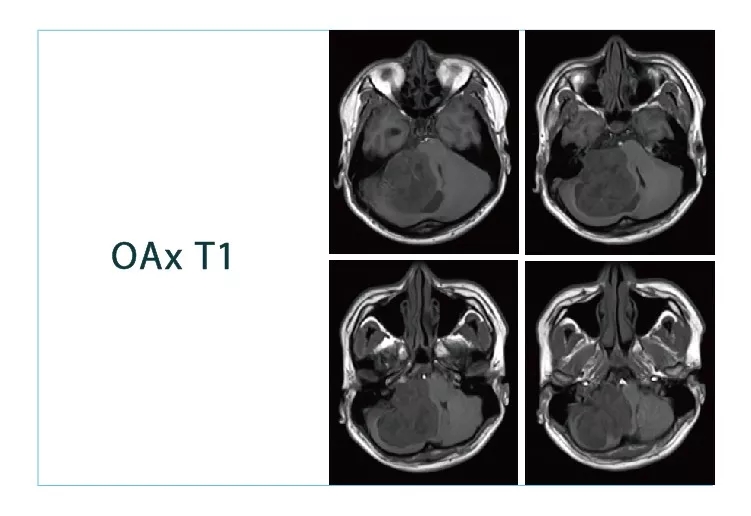

【朗润影像档案】磁共振影像病例分享(编号20180831)